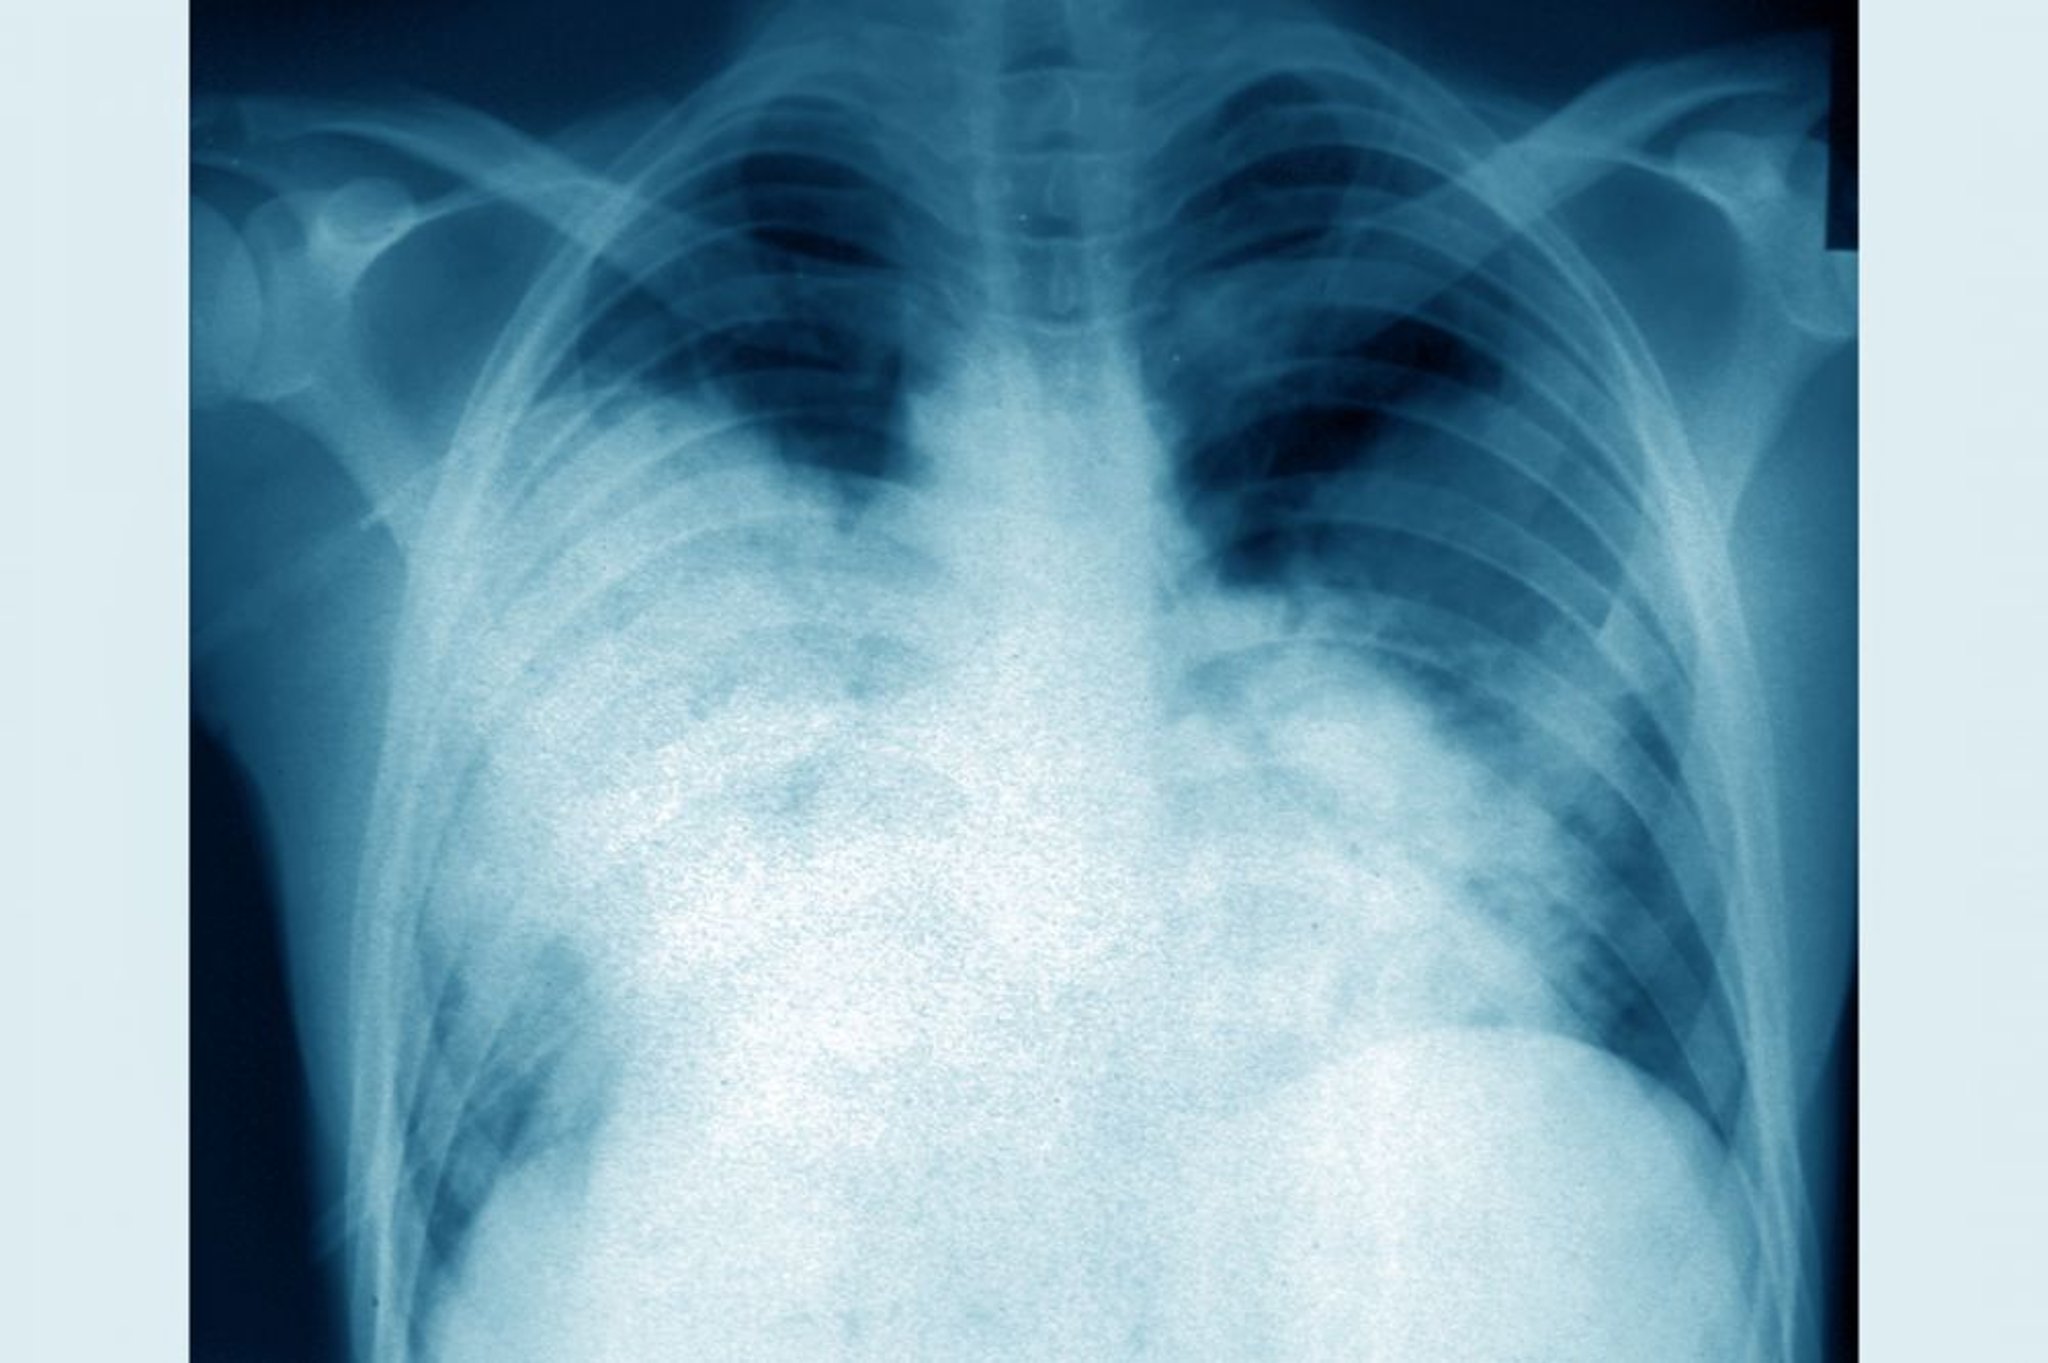

Legionärskrankheit (Röntgenthorax)

Dieses frontale Thoraxröntgenbild zeigt eine akute bilaterale Lungenentzündung (Legionärskrankheit, verursacht durch Legionella pneumophila).